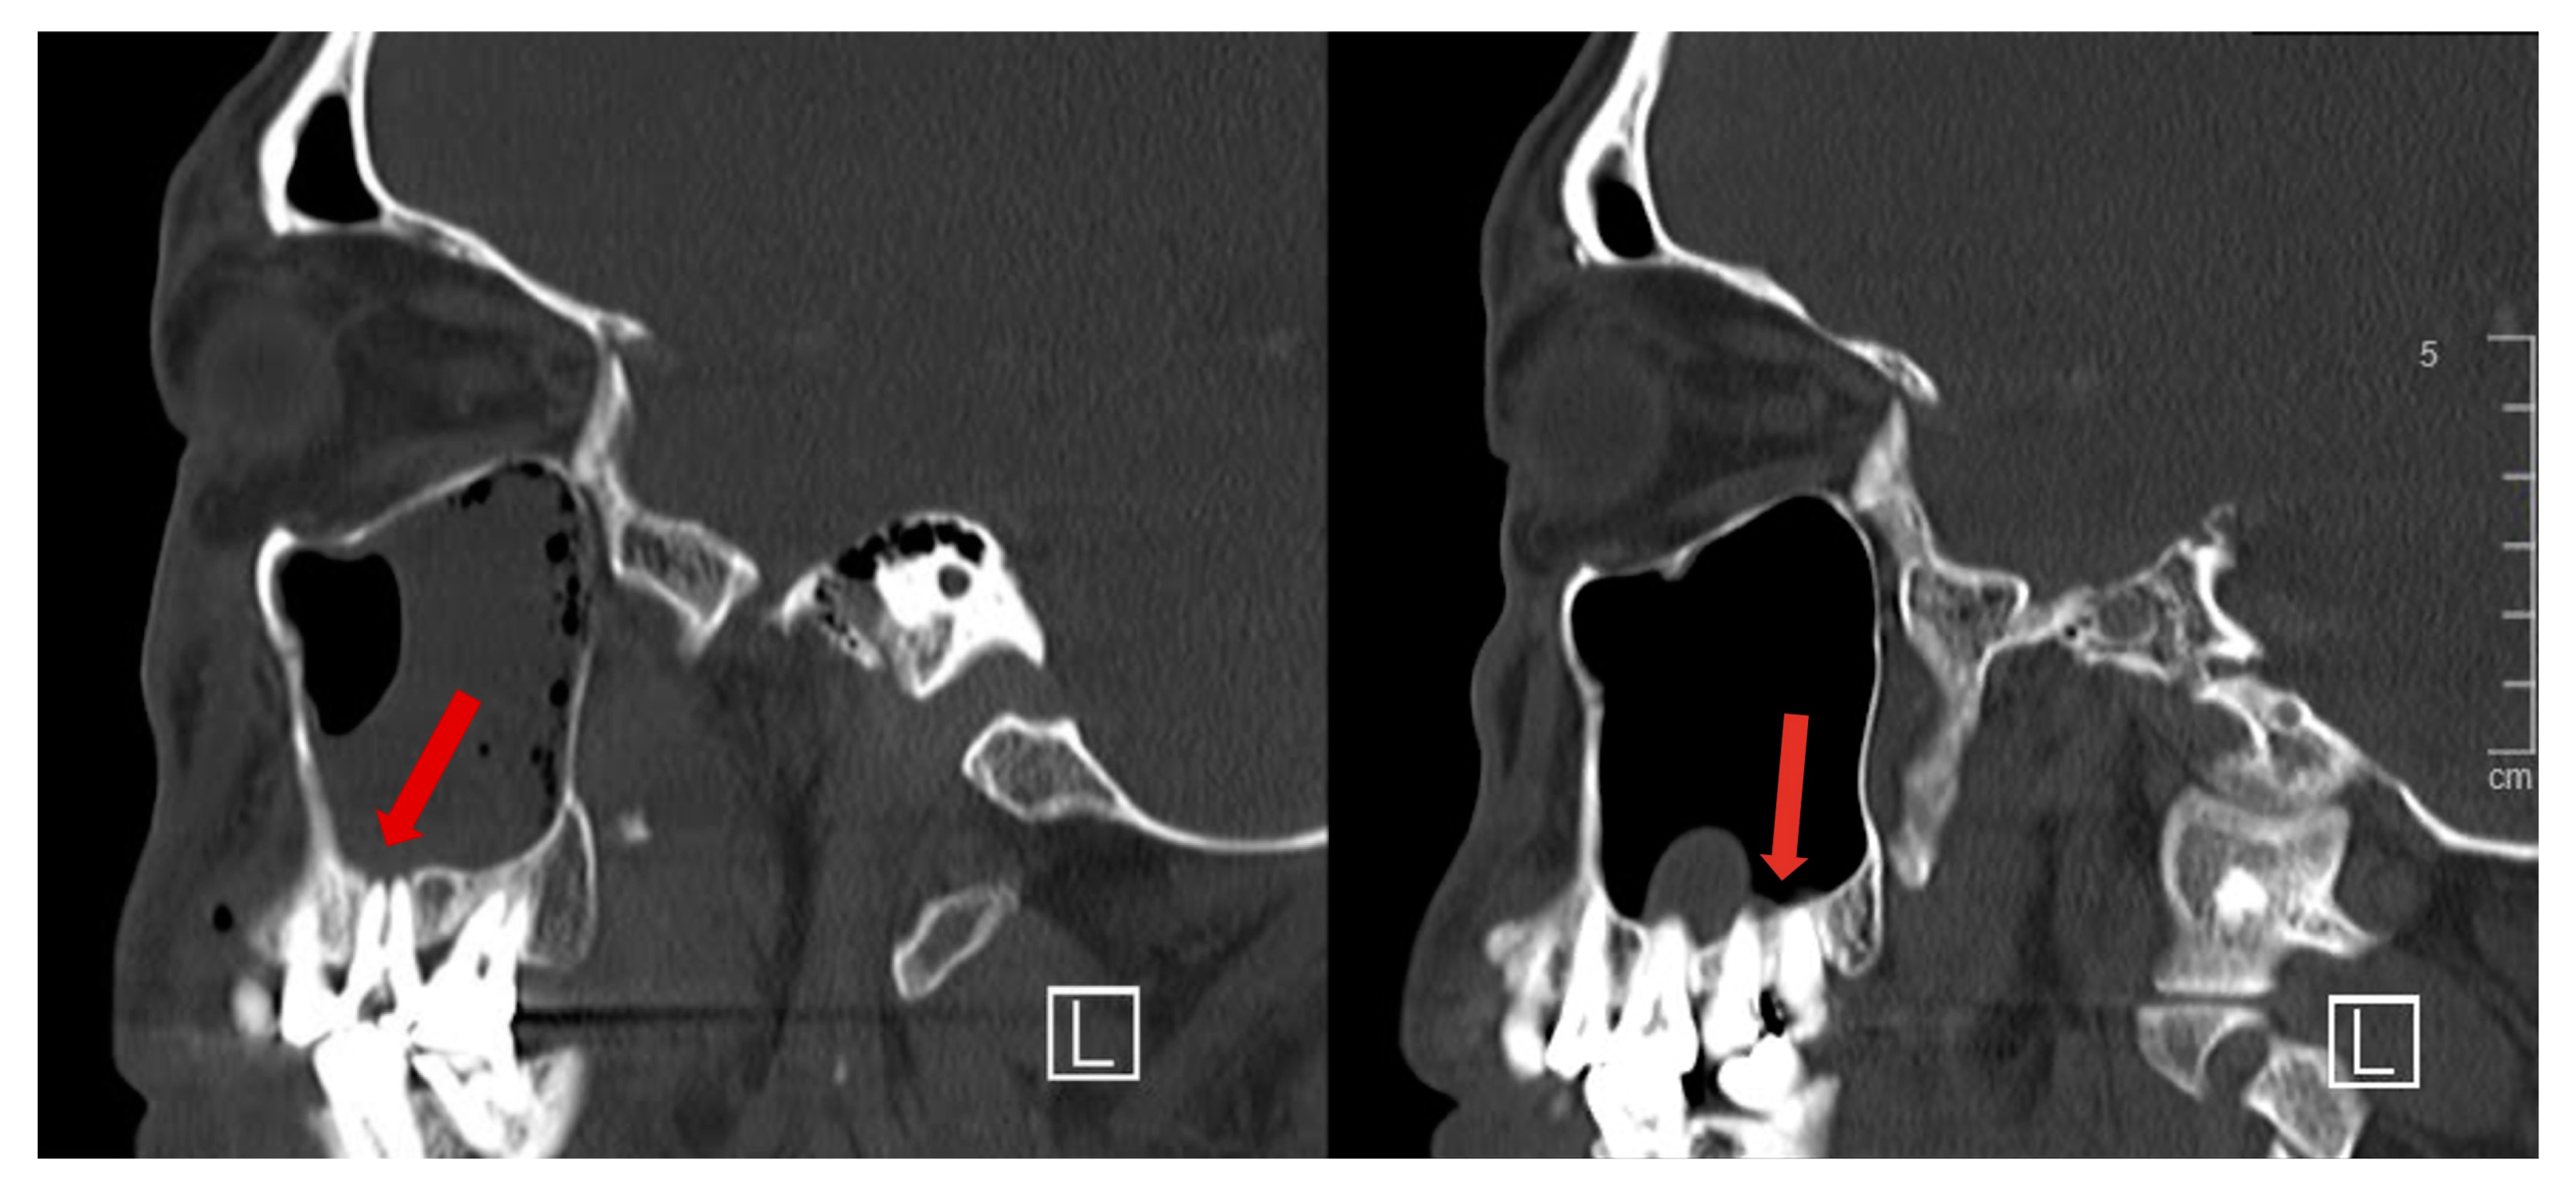

Soft tissue inflammation extended beyond the sinus to involve the orbit superiorly (Figure 2), infratemporal fossa laterally and subcutaneous tissue of the cheek anteriorly. The roots of the second and third maxillary molars were seen protruding into the maxillary sinus (Figure 3).

Figure 3.

Sagittal CT images from the same series showing projection of maxillary tooth roots into the maxillary sinus, with dehiscent overlying bony covering (red arrows).

Hypochlorite accidents involve an undesired introduction of sodium hypochlorite into tissues or spaces beyond the root canal, either via periapical extravasation or accidental spillage. Pre-existing anatomical protrusion of the tooth root into the sinus with a dehiscent or thin overlying bony covering predisposed our patient to periapical extravasation. Poor injection techniques are linked to such accidents. Usage of high concentrations of sodium hypochlorite increases the risk and severity of injury [1,2].